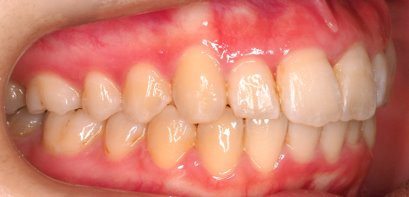

上顎前突といわれ、上顎の前歯が唇側に出ている状態を言います。

前歯が出ることで見た目の問題もありますが、口を閉じることができない、口呼吸をしてしまう、外傷などのリスクがあります。

日本人に叢生の次に多い不正咬合と言われており、自然に治ることはありません。また上の前歯が出ている事だけが気になるかもしれませんが、多くの場合、上顎の奥歯の位置に問題があることが多く、部分矯正でなく根本的な治療をした方がいい場合が殆どです。

口を閉じることができないことで、鼻呼吸でなく口呼吸をしてしまい、結果、成長期の場合顎の骨の成長を邪魔してしまうとも言われております。その他、口呼吸はアトピーなどを含むアレルギー症状の悪化、風邪を含むウイルス性の感染症にかかりやすいなどのリスクも増大してしまいます。

歯並びだけでなく全身への影響も多い為、早期の治療をおすすめ致します。